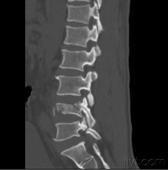

按照Denis三柱概念,爆裂骨折已成為脊柱骨折中具有重要臨床意義的一型,如處理不當(dāng),易引起意外。

Denis等人強(qiáng)調(diào),當(dāng)椎體的后壁和后部纖維環(huán)等結(jié)構(gòu),即包括后縱韌帶的中柱一旦遭受破壞,則可造成前屈狀態(tài)下的不穩(wěn)定,并把此種累及前柱和中柱的骨折定義為爆裂骨折。